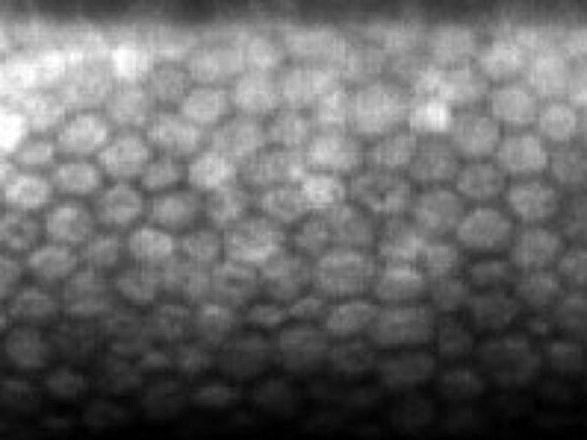

細胞がきれいな六角形を保ち、きちんと整列しています。(角膜内皮細胞解析装置による画像)

細胞の一部が死滅し、それを埋めるために細胞が肥大・変形しています。(角膜内皮細胞解析装置による画像)